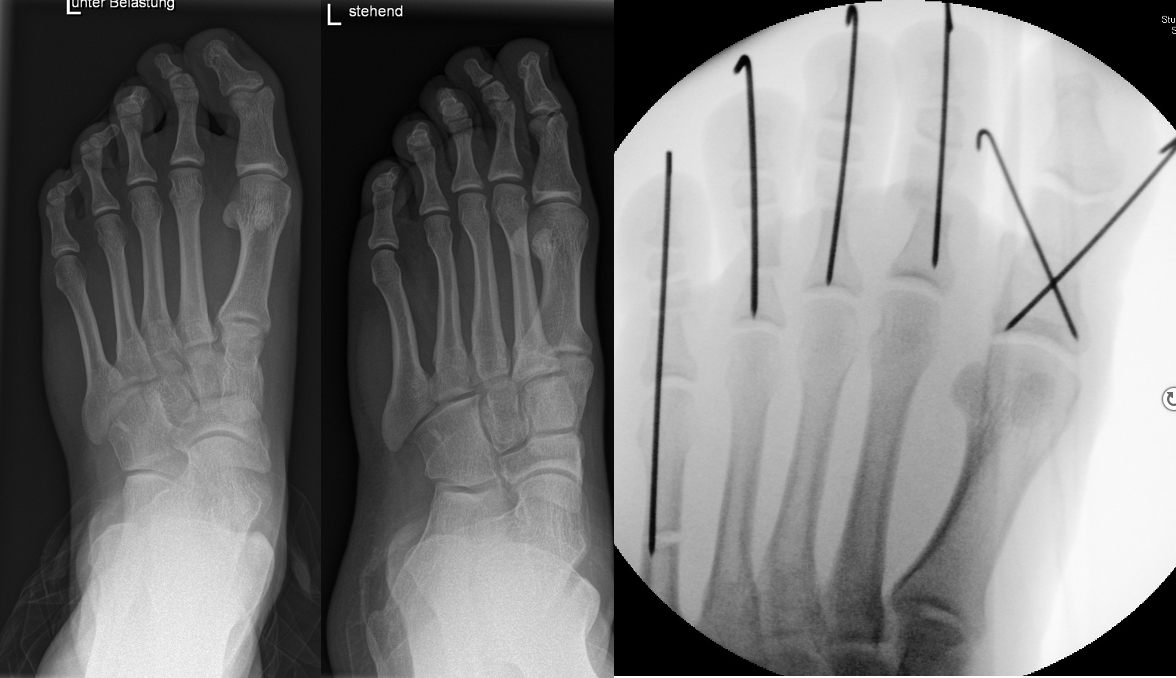

Abb. 2 a-c: offene Wachstumsfugen MT I Basis und Zehen (a), teilweise geöffnete Wachstumsfugen (b) und geschlossene Wachstumsfugen (c).

Zum Lesen der Bildbeschreibung und zur Vollansicht bitte die Bilder anklicken. Bilder: A. Helmers.

Die erforderlichen Osteotomien sind daher dem Fugenverlauf anzupassen, diese sind unbedingt zu respektieren. Wird eine Wachstumsfuge versehentlich mit der Fräse verletzt, kann durch partiellen oder kompletten Fugenverschluss ein Fehlwachstum provoziert werden. Achsabweichungen oder ein Wachstumstopp der betroffenen Region können die Folge sein. Offene Wachstumsfugen begrenzen die Osteotomieausrichtung besonders im Bereich des dorsalen Calcaneus, der Metatarsale I Basis und der IV. oder V. Zehe im End- und Mittelglied.

Zusätzlich schränken Wachstumsfugen die Wahl der Osteosynthese ein. Eine die Fuge kreuzende Osteosynthese ist ausschließlich mit Kirschner-Drähten möglich (Abb. 3).